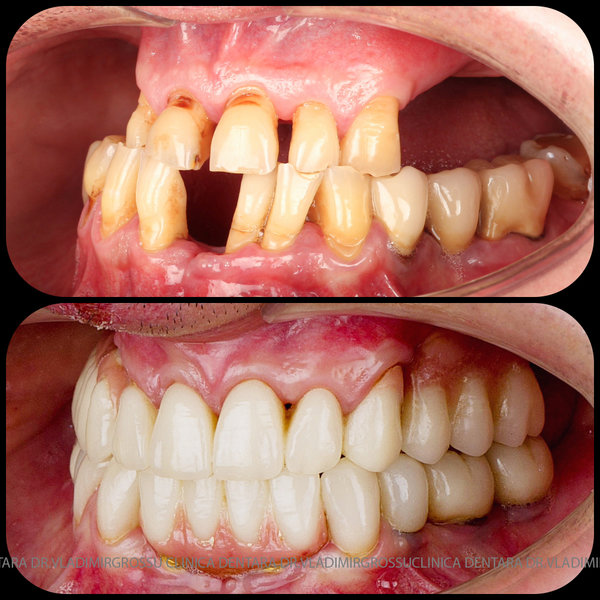

Cazuri clinice conceptul All-on-6

Caz 1